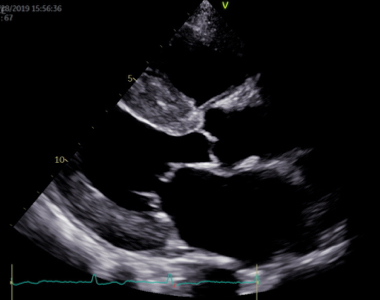

心エコー図検査は体に害のない、痛みを伴わない検査です。どの弁が障害されているのかを特定し、その動きや狭窄・逆流の程度を診断します。同時に、心臓の部屋の大きさや機能を診断しますが、これらは治療方針に直結します。体に負担のない検査なので、治療後に繰り返し検査をして、どの程度改善しているかを評価することもできます。さらに、手術が必要な方には、心臓血管外科医が手術を行う際に必要となる様々な情報を提供します。

心臓の形や大きさ、動きの程度などが正確にわかります。